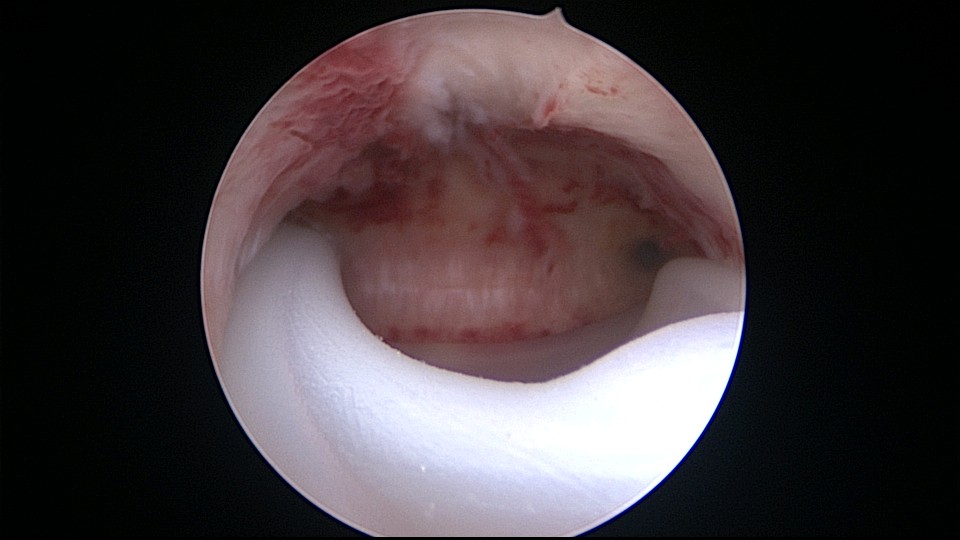

患者34岁,G4P1,顺产1次,继发不孕,宫腔容积小,宫腔粘连。2020年9月宫腔镜探查,见宫腔下段幕状粘连,两侧小孔与宫腔上段相通,形成假的输卵管开口。双极电针切开粘连,宫腔形态恢复正常,显露双侧输卵管正常开口。2020年10月宫腔镜二探取球囊,宫腔形态正常,双侧输卵管开口可见。2021年6月自然妊娠,2022年2月足月剖宫产分娩,2023年5月再次妊娠1次,人流终止妊娠。现39岁,G6P2,顺产1次,剖宫产1次。